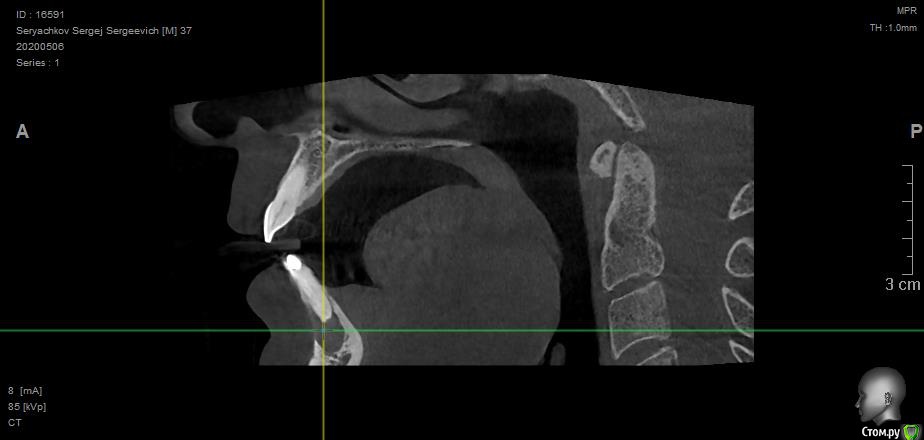

olstrill Опубликовано 24 мая, 2020 Поделиться Опубликовано 24 мая, 2020 Добрый день. Под передними резцами обнаружилась обширная киста. В трёх клиниках предложили различное решение:1. Удаление 2-х поражённых зубов, разбираемся с кистой, ждём полгода, потом вкручиваем Dentium Implantium. На период ожидания верхняя часть вырванных зубов крепится на пластинку, которая как-то крепится на соседние зубы, нагрузка на заглушки до установки имплантов запрещена.2. Удаление 6-ти передних зубов (включая клыки), установка на их место 3-х Dentium Implantium + коронка на 6 удалённых зубов. Врач говорит - как удалим зубы сразу поставим временную коронку, мол эстетически будет самое лучшее решение, а также это самый быстрый вариант, мол пару месяцев - и готово.3. Удаление 2-х поражённых зубов, обточка соседних и установка на шесть передних длинной коронки. Средний вариант по срокам и стоимости. Склоняюсь к первому варианту, но волнуют следующие вопросы:1. Под повреждёнными зубами, как я понимаю, нету или мало кости, в которой можно было бы закрепить импланты. Что там нарастёт за полгода ожидания непонятно. Врач говорит, что нужно будет ещё дополнительно наращивать кость, но не будет ли это половинчатым решением? Подозреваю, что импланты будут подвижны, что, как я понимаю, не хорошо.2. Импланты в зоне улыбки могут эстетически выглядеть не очень, к тому же могут просвечивать через десну.3. Будут слабо выражены переходы между имплантами, десна там может принять прямую форму, что эстетически будет смотреться так себе.3. Временные зубы на месте вырванных на период восстановления кости, врач говорит - периодически будешь приходить и будем править тебе пластинку с "заглушками". Думаю потеряю я эту пластинку в первую неделю и буду ходить полгода с дырой впереди (что, в связи с работой, неприемлемо). Хотелось бы услышать мнение экспертов - правильные ли предложены методы решения проблемы и обоснованны ли переживания. Ссылка на комментарий